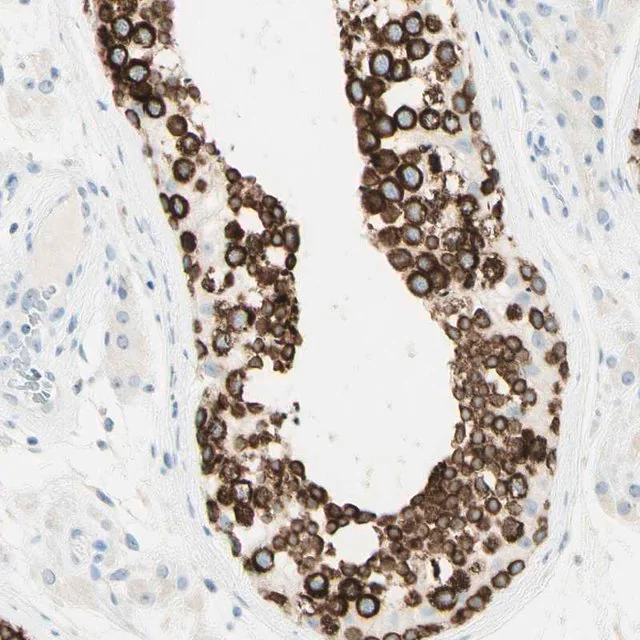

| Application【应用】 | Anti-FMR1NB antibody produced in rabbit, a Prestige Antibody, is developed and validated by the Human Protein Atlas (HPA) project (www.proteinatlas.org). Each antibody is tested by immunohistochemistry against hundreds of normal and disease tissues. These images can be viewed on the Human Protein Atlas (HPA) site by clicking on the Image Gallery link. The antibodies are also tested using immunofluorescence and western blotting. To view these protocols and other useful information about Prestige Antibodies and the HPA, visit sigma.com/prestige. |

| General description【一般描述】 | FMR1NB (fragile X mental retardation 1 neighbor) is an antigen associated with cancer and testis. It is specifically expressed in normal testis and in multiple cancers. This gene is localized to human chromosome Xq28, and codes for a predicted secreted or cell surface protein. This gene has six exons, spans ~44kb. The open reading frame codes for a protein with 255 amino acids, and a predicted molecular mass of 29.2kDa. The protein contains a transmembrane region and a signal peptide. It has a cysteine-rich trefoil/P-domain, which is characteristic of multiple secreted proteins. It does not belong to any known gene family. |